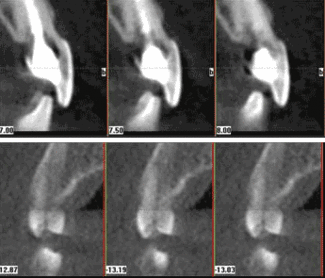

It's frustrating when we suspect a crack and perform a certain procedure, only to hear the patient has returned and we have to try again. With a cone beam scan, we can detect small cracks and correctly determine whether to re-treat or not. This avoids unnecessary surgery (Fig. 2).